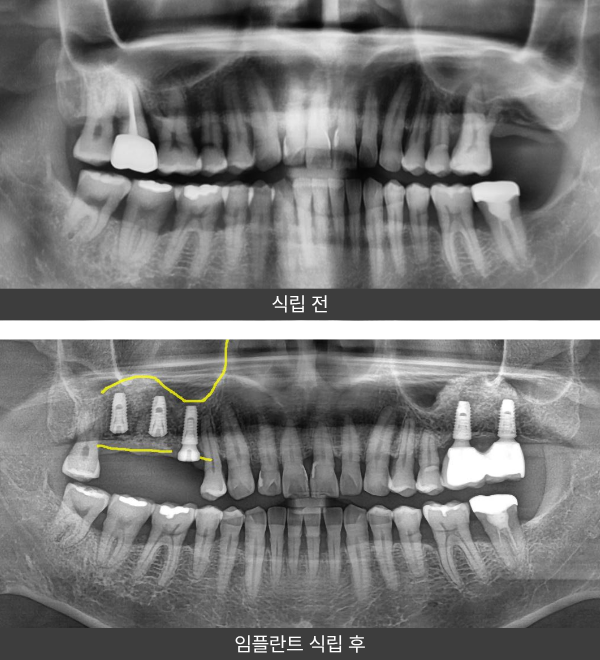

상악동거상술 임플란트

사례 2

“좌우 상악동 모두 뼈가 부족해 양측 동시 수술이

필요했던 분이셨습니다.

좌우 상악 어금니 부위 모두 잔존골이 부족한 상태로,

한쪽이 아닌 양측 모두 상악동거상술이 필요한 상황이었습니다.

상악동이 아래로 내려와 있어 임플란트를 식립할 수 있는

뼈의 높이가 충분하지 않아, 좌우 상악동을 동시에 거상한 뒤

충분한 골 이식을 진행하고 임플란트를 식립하였습니다.

환자 분께서는 양쪽 모두 수술이 필요하다는 설명에 부담을 느끼셨고,

치료 과정과 회복에 대한 걱정이 많으셨습니다.

양측 상악동거상술과 뼈이식을 동시에 진행한 뒤 임플란트를 식립하였고,

현재는 임플란트가 안정적으로 자리 잡아 기능적으로

잘 유지되며 만족스러운 상태를 보이고 계십니다.